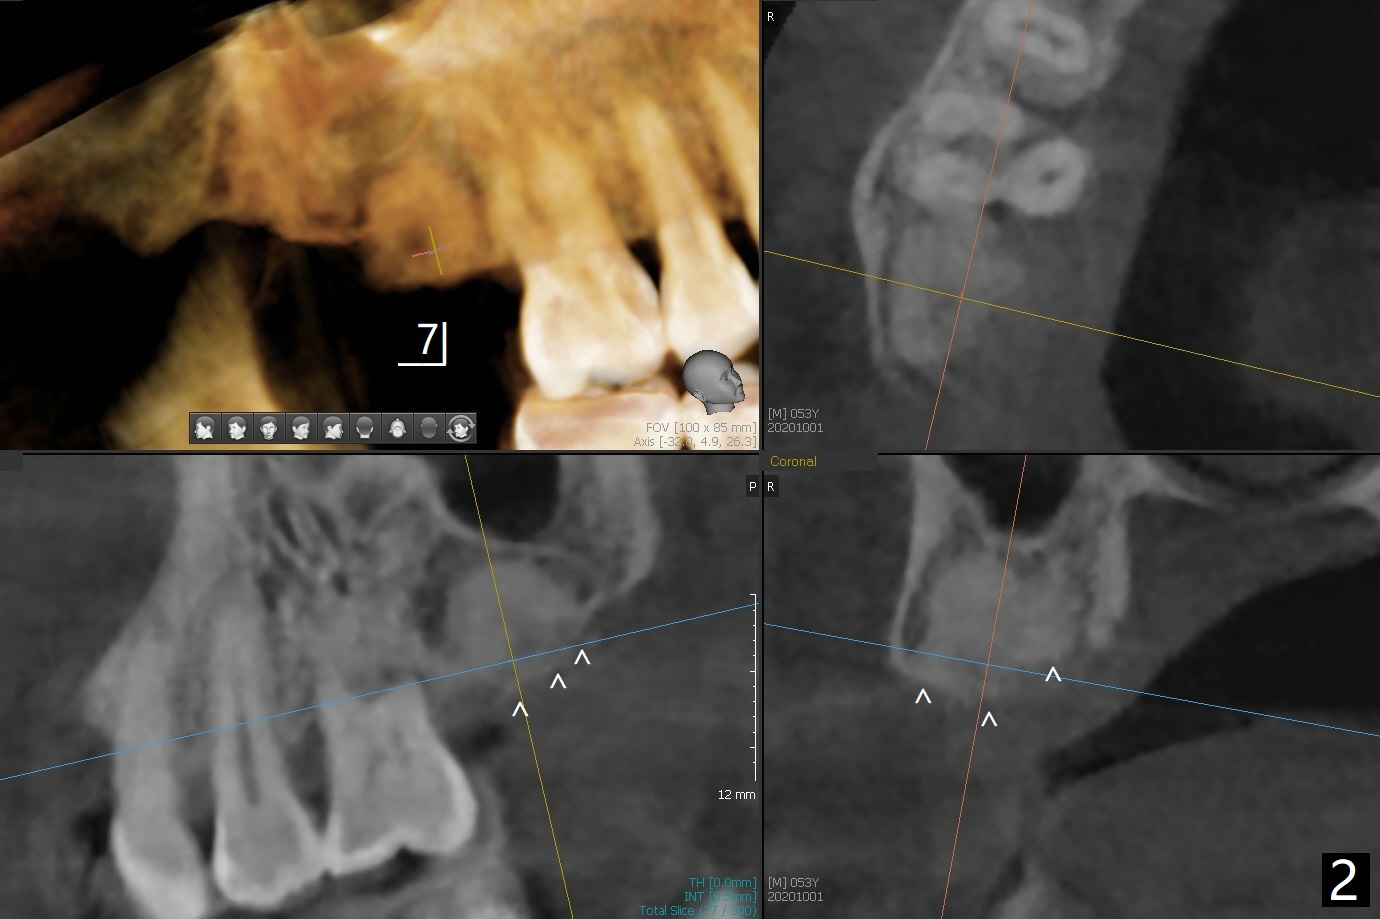

53岁男一年前在别的诊所做右上7拔牙植骨,现在要求植牙(图一),其余牙齿骨质吸收严重,植牙更显得重要。缺牙区植骨密度正常,但是牙槽嵴不平(图二:箭头),导板种植,植体可能偏向低处(阻力低的区域:远中,腭侧(图三:箭头)),几年后可能出现螺纹暴露